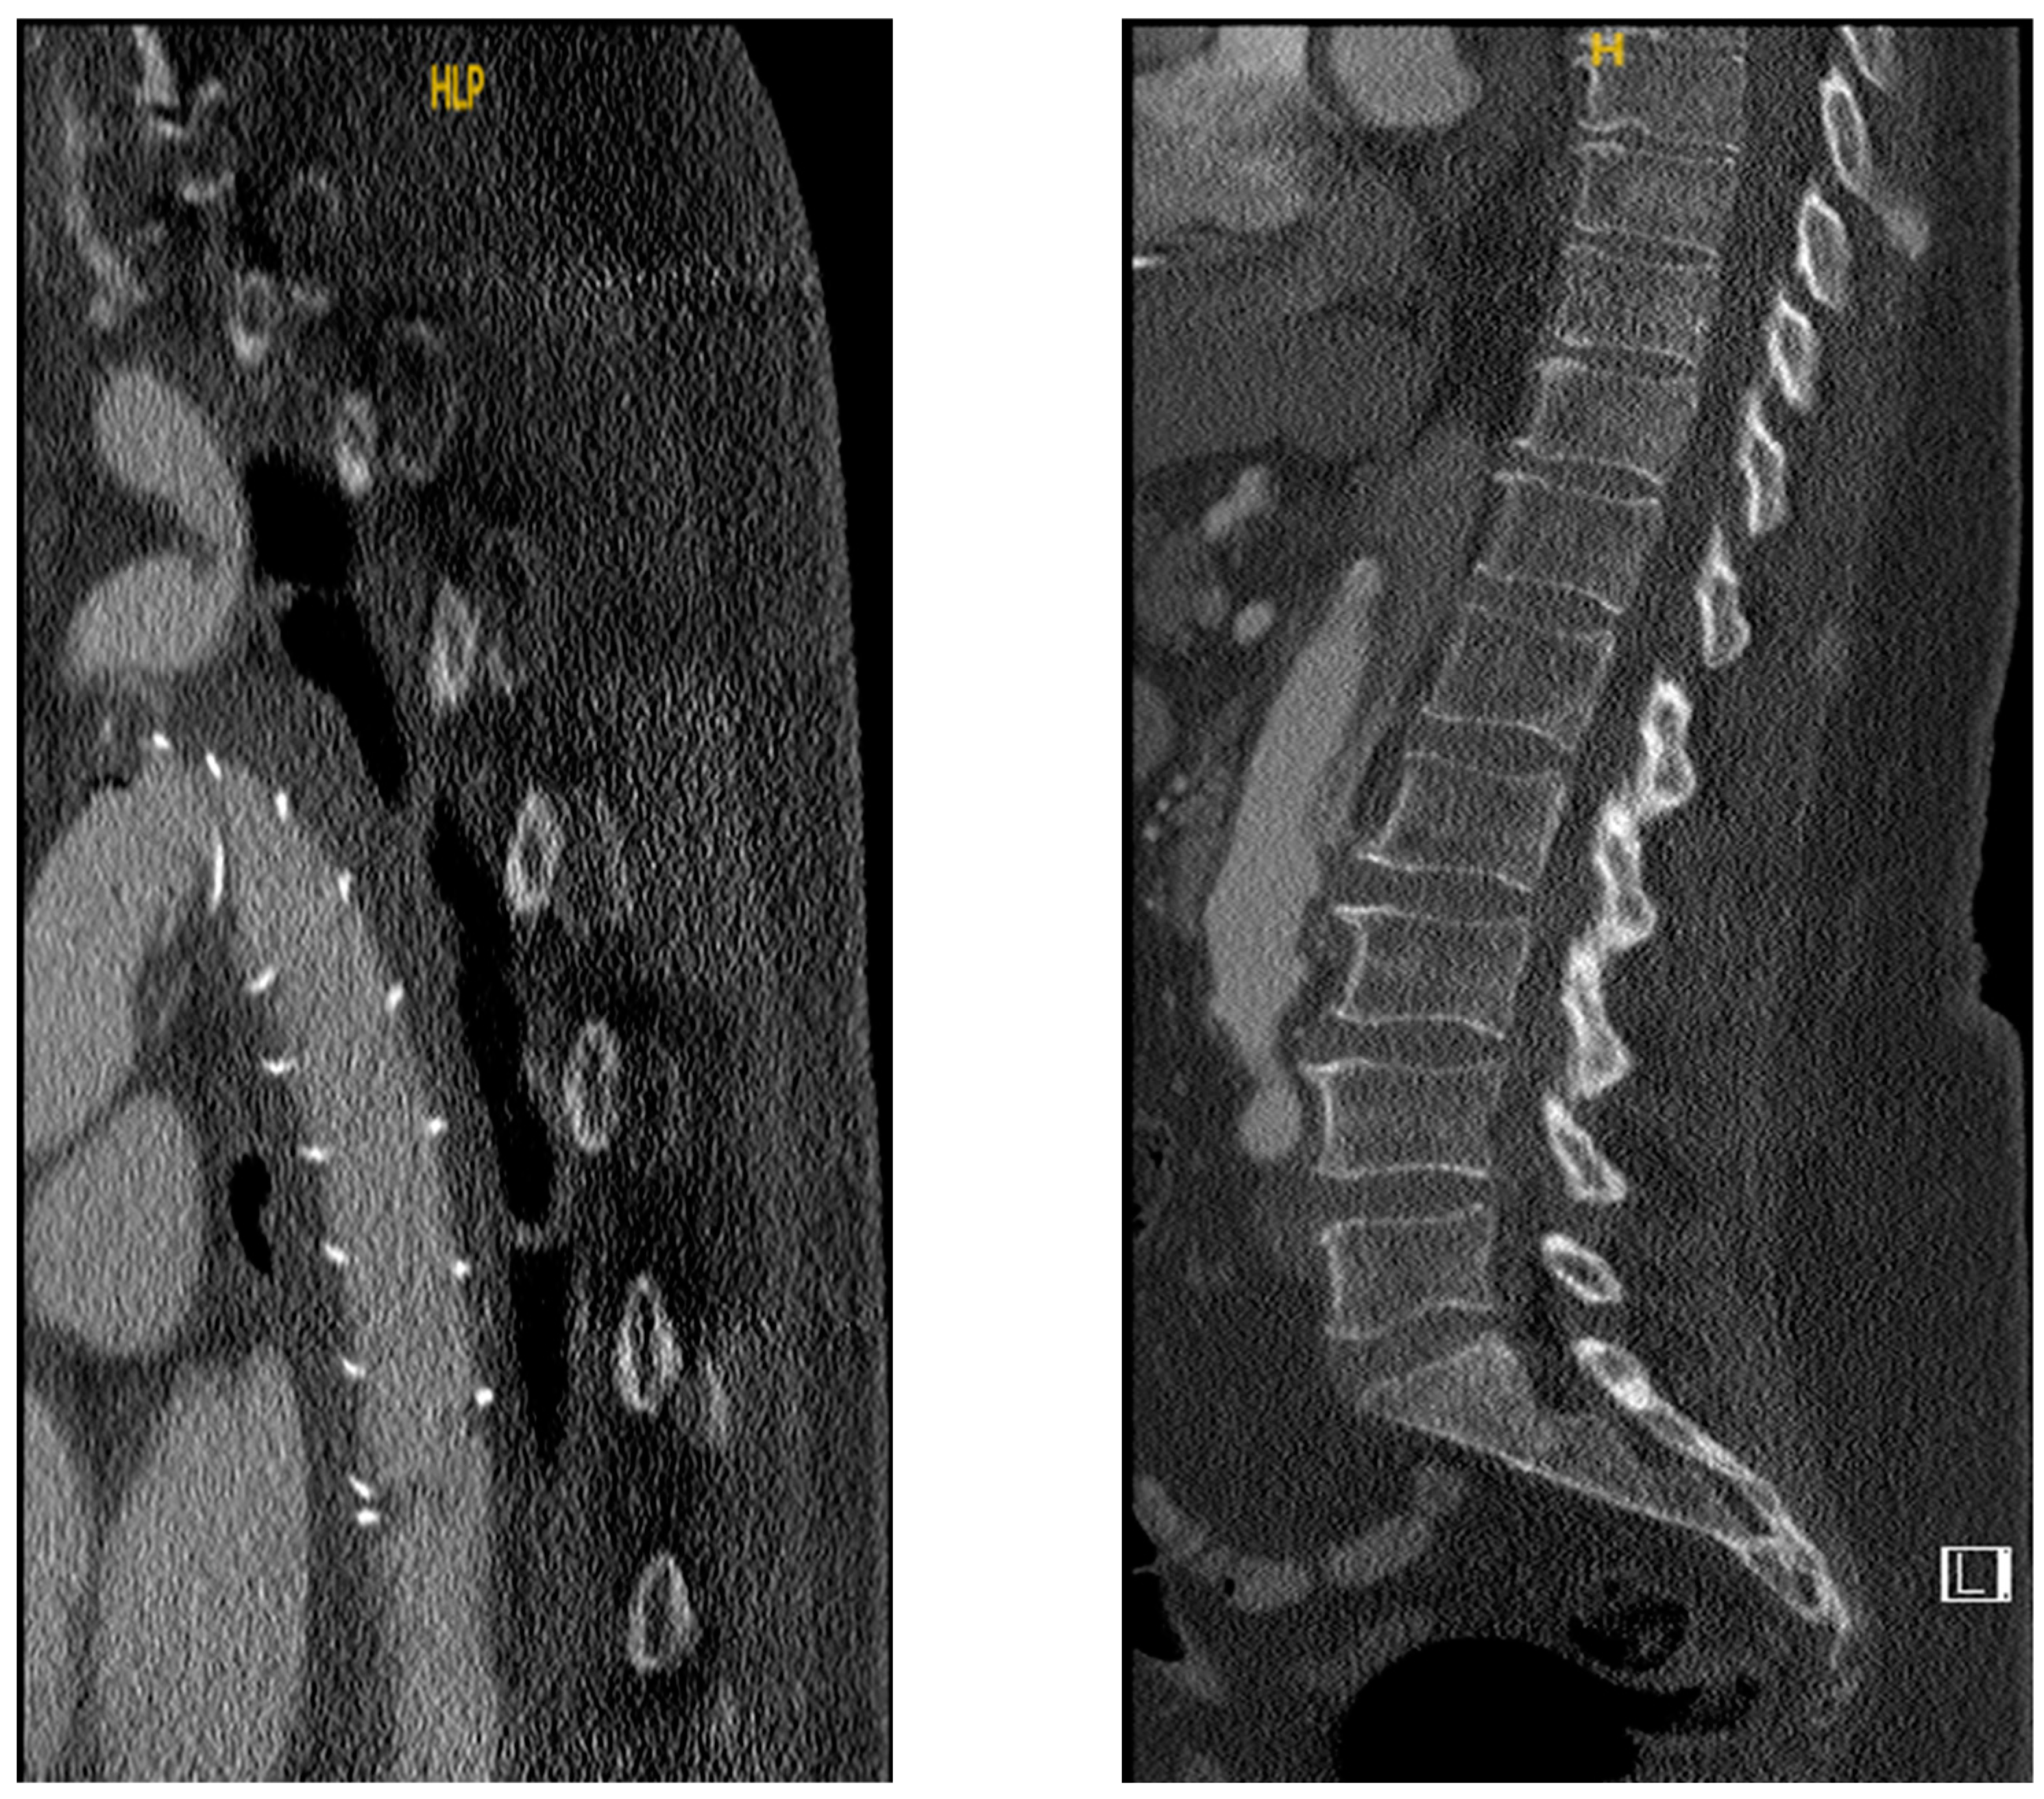

3. Results